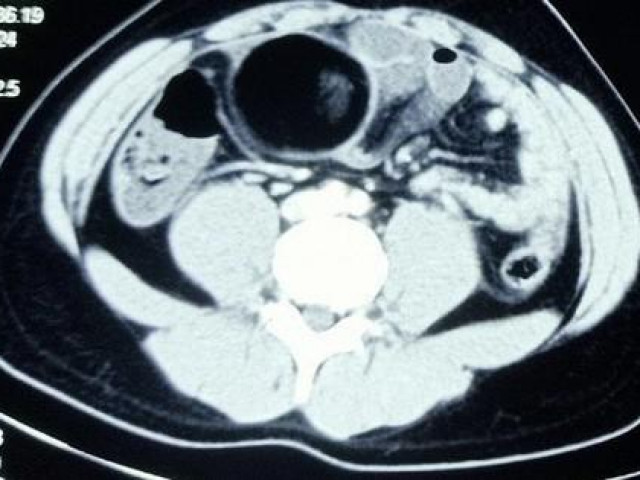

Khi ông Li được đưa vào viện, bác sĩ vội vàng tiến hành chụp CT sọ não cho ông, kết quả cho thấy nhiều mạch máu trong não bị vỡ, chẩn đoán xuất huyết não cấp. Sau hơn 3 giờ cấp cứu, bệnh nhân đã tử vong do chảy máu quá nhiều.